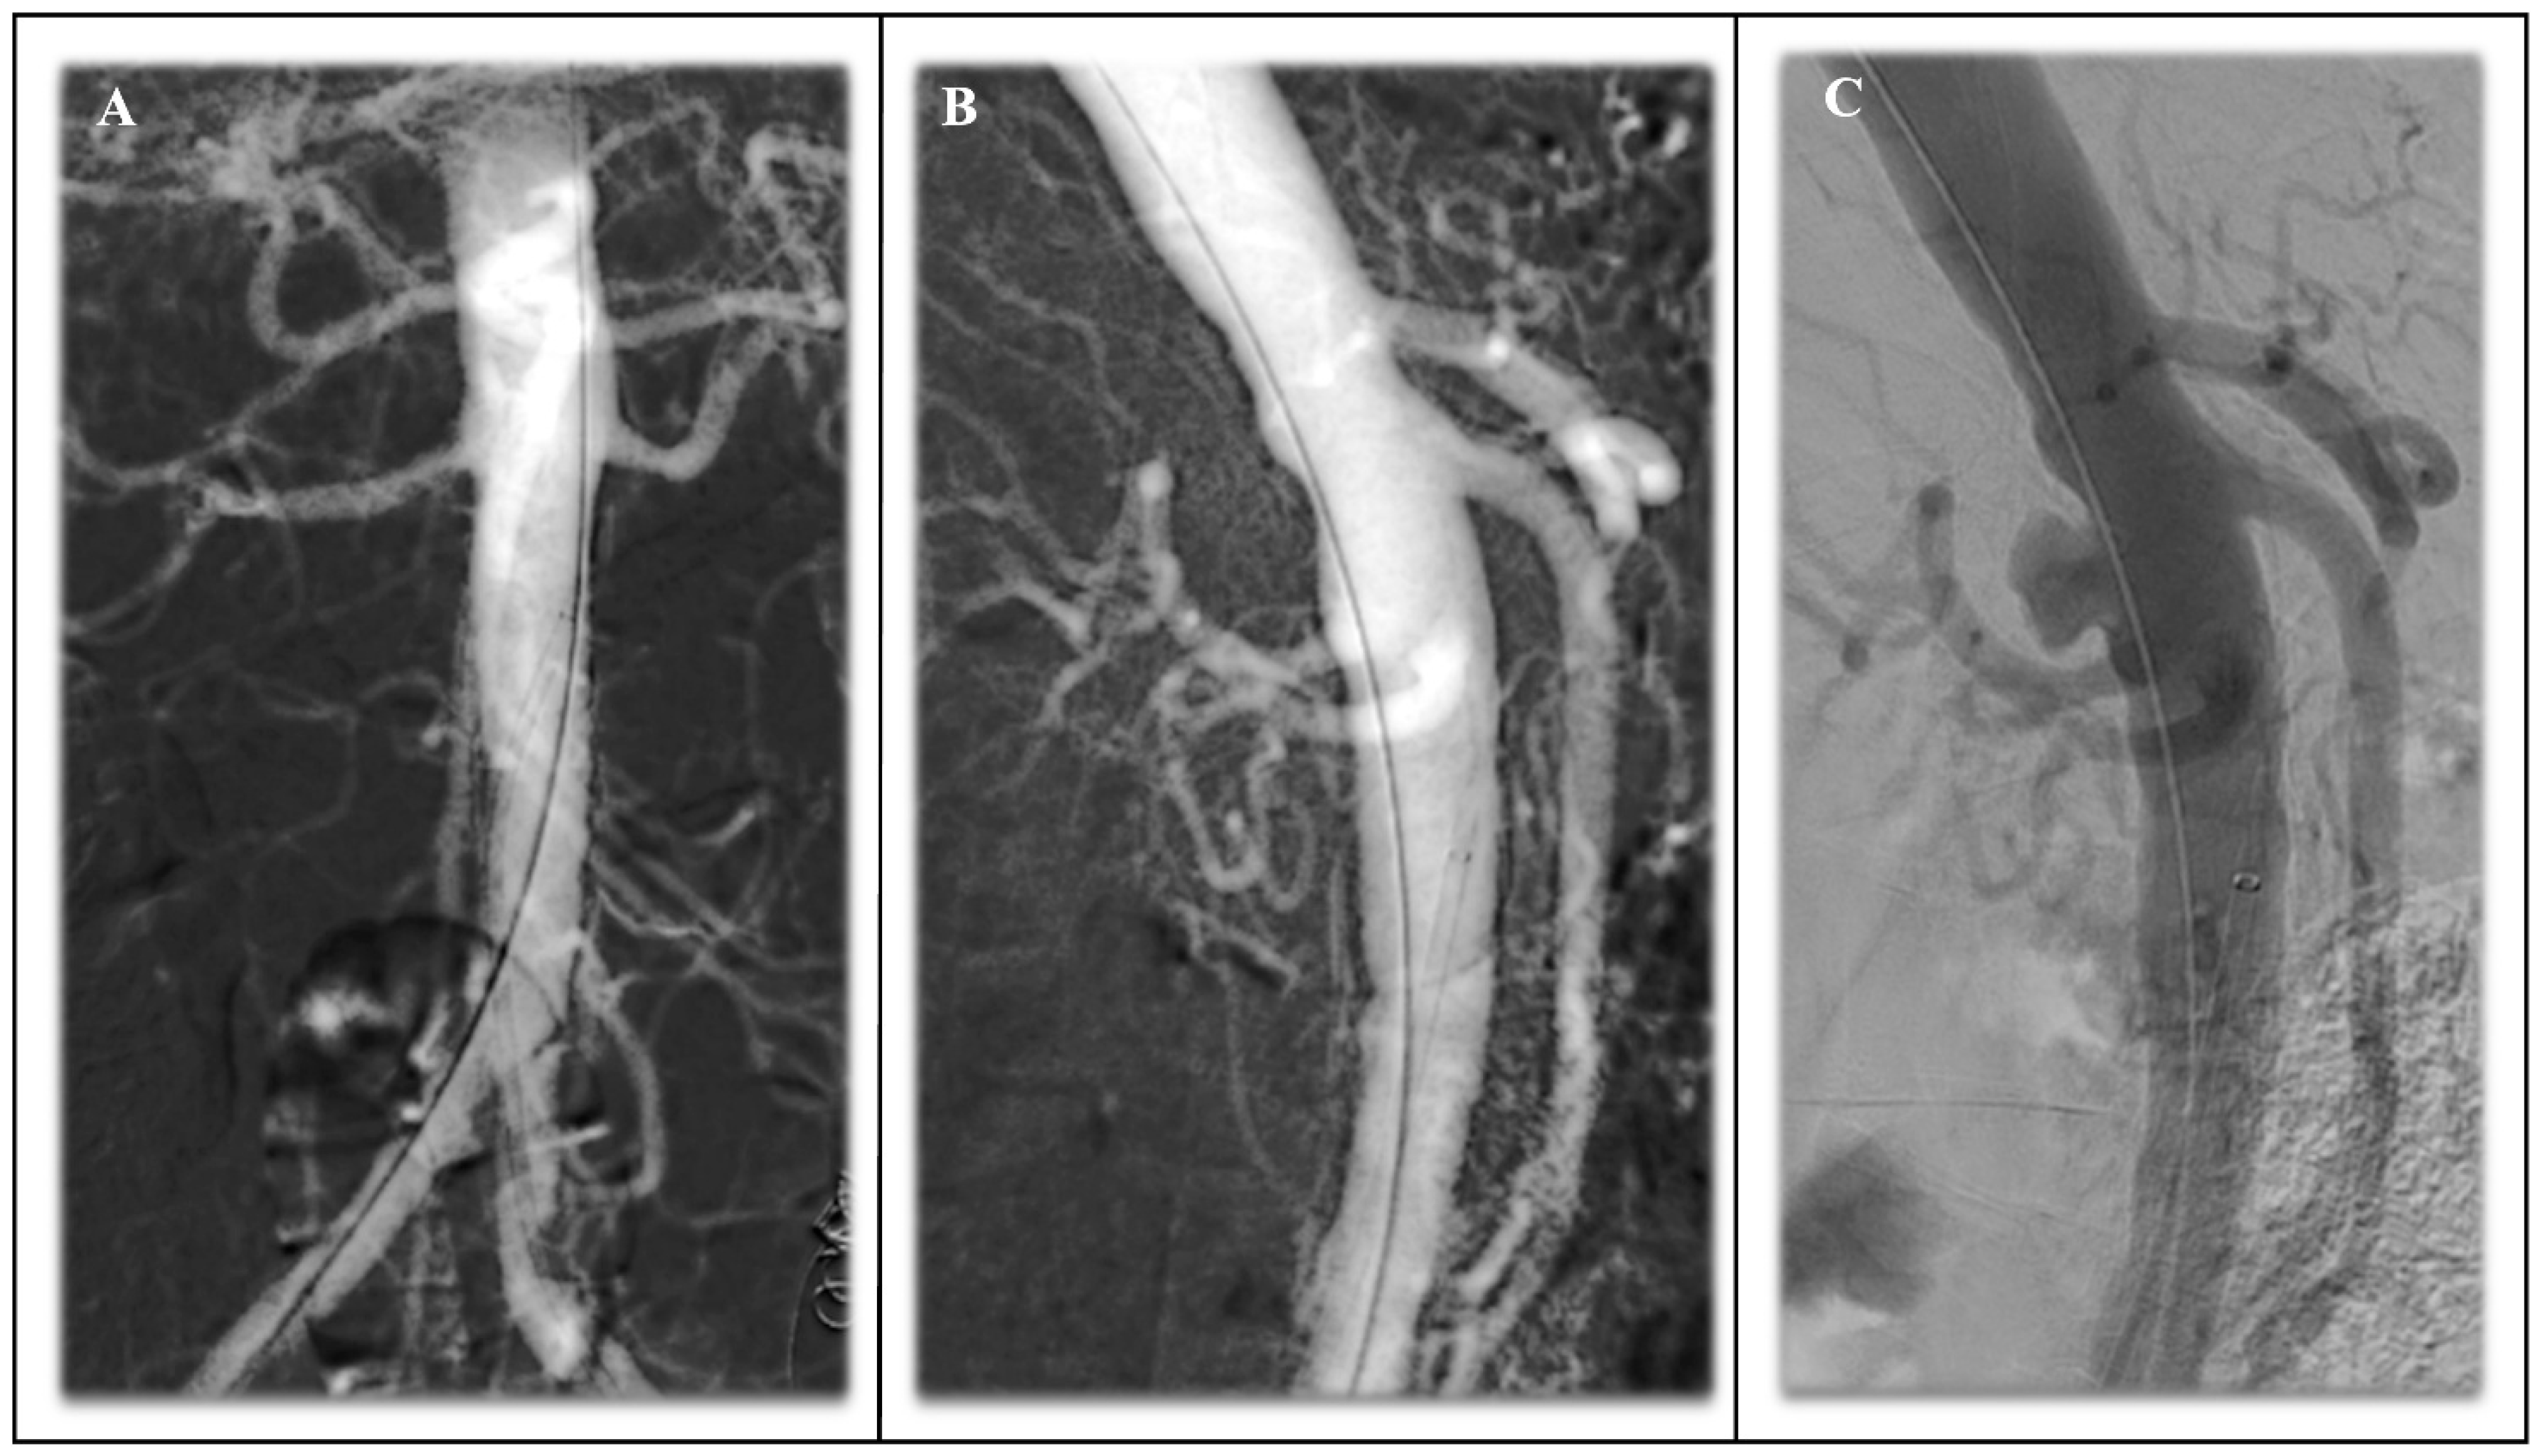

4.1. Infrarenal EVAR